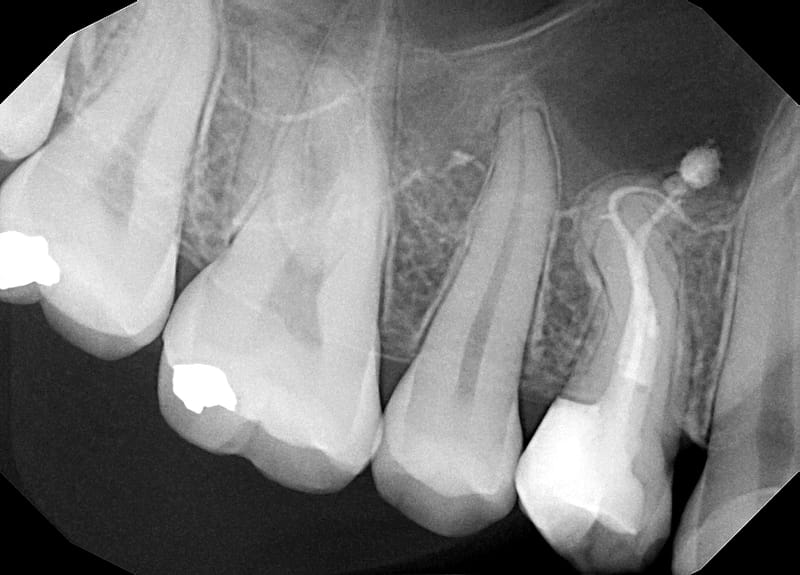

Leczenie pierwotne d.24